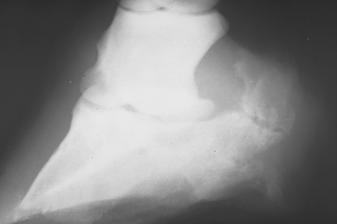

Analizuojant OCD pasireiškimą kulno sąnaryje, atvejų dažnumas kairėje ir dešinėje pusėse gana ženkliai skyrėsi. Kairės pusės pažeidimai buvo nustatyti 14 atvejų, kai tuo tarpu dešiniosios – 7, t.y., kairės pusės kulno sąnario osteochondritiniai pažeidimai nustatyti du kartus dažniau.

Tyrimui buvo surinktos rentgenogramos, kuriose atliktos kulno sąnario projekcijos 45-70o, 110-120o kryptimis. Kulno sanaryje OCD fragmentų dydis svyravo nuo pipiro iki vyšnios dydžio. Tai buvo pastebima tiek 47-70o, tiek 110-120o projekcijose. Osteochondritiniai fragmentai kulno sąnaryje buvo matomi kaip atplaišos nelygiais kontūrais, taip pat buvo rasti nelygūs sąnariniai paviršiai.

26 pav. Kulno sąnario rentgenograma